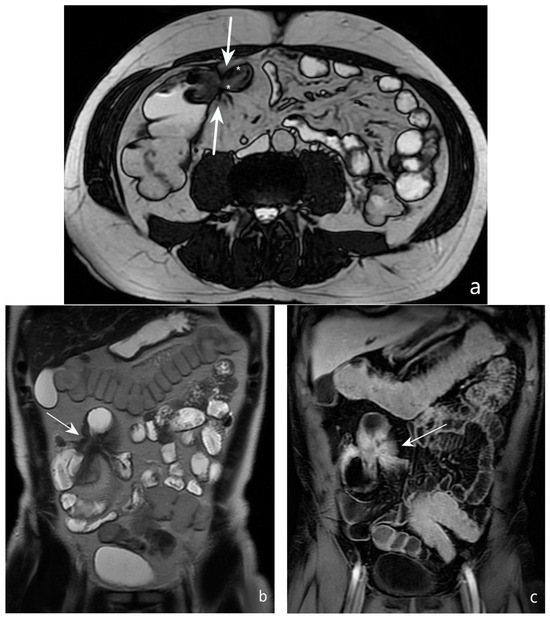

9. Is It Possible to Assess Post-Operative Recurrence?